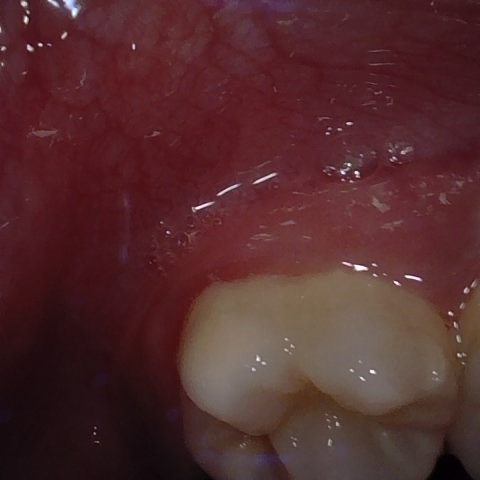

Annotated as "Good"